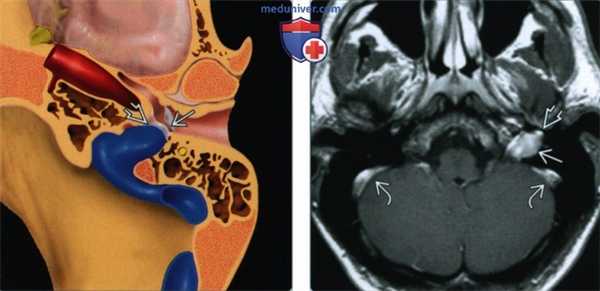

(Слева) На рисунке аксиального среза показана дегисценция луковицы яремной вены: через дефект в сигмовидной пластинке она пролабирует в верхнелатеральном направлении в барабанную полость. Как правило, в задненижнем квадранте за интактной барабанной перепонкой визуализируется сосудистое «объемное образование» синего цвета.

(Справа) При МРТ Т1 ВИ с КУ в аксиальной проекции отмечается контрастирование расширенной луковицы яремной вены, сообщающейся с пролабирующим в барабанную полость компонентом. Аналогично контрастируются и сигмовидные синусы.

(Слева) При аксиальной КТ в коаном окне определяются луковица яремной вены и мягкотканной плотности объемное образование в нижней части правой барабанной полости, сообщающиеся через широкий дефект яремной пластинки.

(Справа) При корональной КТ в костном окне определяется дольчатое выпячивание луковицы яремной вены в правую барабанную полость. Дегисценция луковицы яремной вены -наиболее часто варечающаяся сосудистая аномалия височной кости; чаще она выявляется справа.